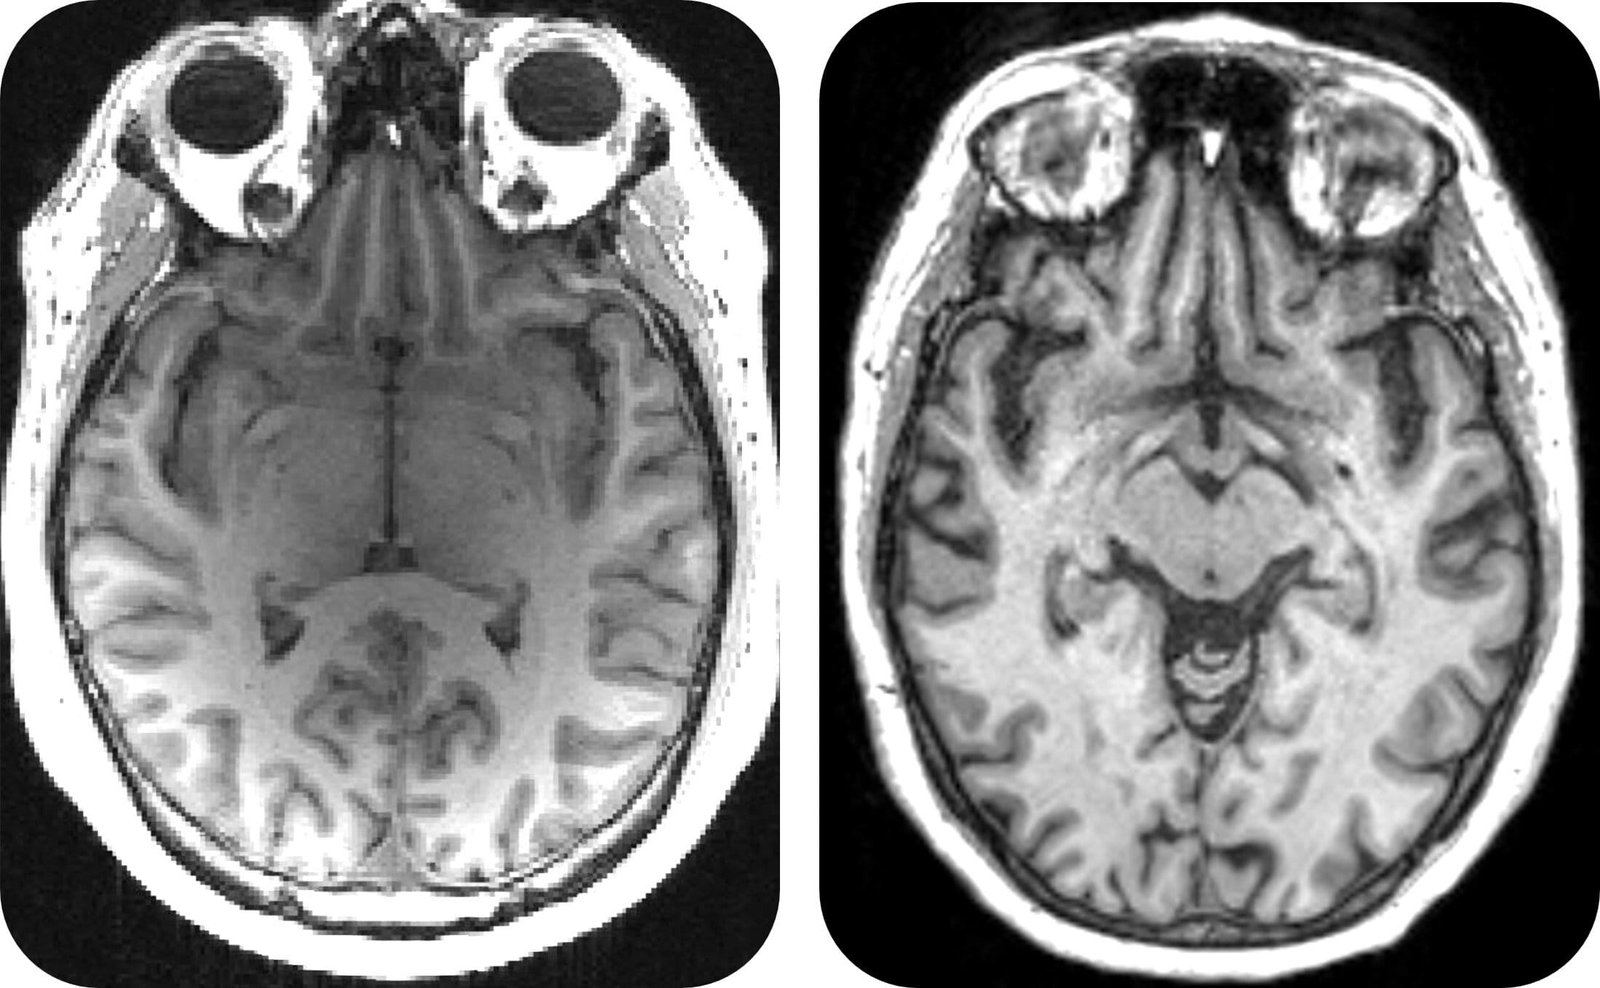

The AI model, developed by researchers in Cambridge’s Department of Psychology, functions like a highly-trained observer, able to detect subtle, early warning signs that would elude even seasoned clinicians. Using inputs from MRI scans, cognitive assessments, and blood biomarkers, the model generates a score predicting how quickly an individual will progress toward full-blown Alzheimer’s disease.